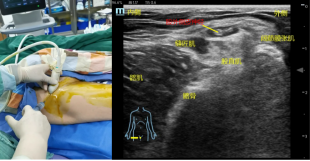

超声准备:高频探头、神经肌肉模式。体位:仰卧位。

扫查方法:①向下扫查:探头放置于髂前上棘,然后上下滑动,找外侧的缝匠肌和内侧的阔筋膜张肌,股外侧皮神经位于两层肌肉之间的表面。②向上扫查:先在股骨中段找表浅的股动脉,往上滑动找并追踪缝匠肌,然后探头往外,找阔筋膜张肌,在两肌之间往上找股外侧皮神经。

穿刺方法:平面内法,从大腿外侧进针,①在腹股沟韧带水平注射时,药物注射在髂前上棘内1-2cm,髂腰肌的浅层。②在缝匠肌水平注射时,药物注射在缝匠肌和阔筋膜张肌的表面。